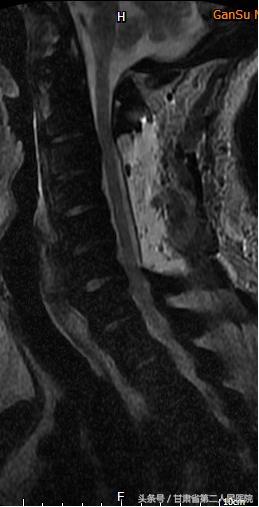

1月25日,省二院骨科袁治国主任、白登彦副主任带领医护团队,在手术麻醉科医护人员的大力配合下,历时5小时,出血不到100ML,顺利完成了“C3-6后路椎板切除钉棒系统内固定术”。

术后